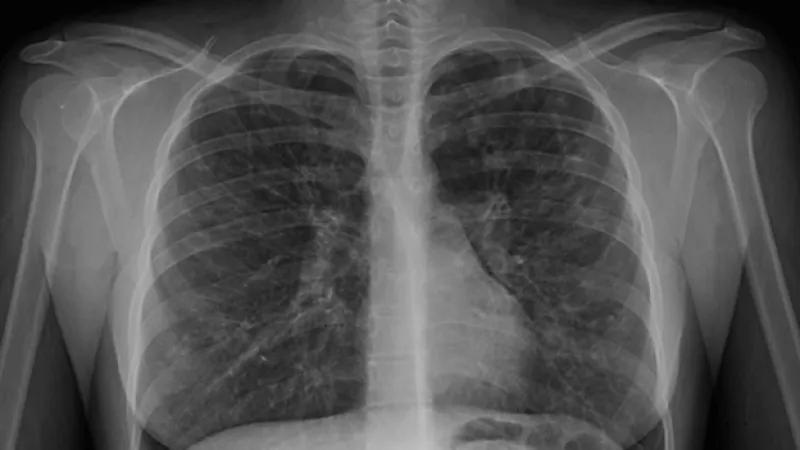

pulmones radiografia fibrosis

Las fibras microscópicas de asbesto pueden incrustarse en el tejido pulmonar y causar enfermedades graves en los pulmones y problemas respiratorios.

La asbestosis es un trastorno de respiración  causado por inhalar fibras de asbesto . La acumulación prolongada de estas fibras en los pulmones puede causar cicatrices en el tejido pulmonar y dificultad para respirar. Los síntomas de la asbestosis pueden variar de leves a graves, y usualmente no aparecen hasta muchos años después de la exposición. Si fumas y tienes asbestosis, la probabilidad de desarrollar cáncer de pulmón aumenta en gran medida. El humo del tabaco y el asbesto parecen contribuir a los efectos causantes de cáncer entre sí, según la Clínica Mayo.